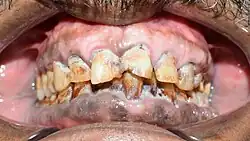

Salud bucal

El tabaco también afecta la salud bucal. La melanosis del fumador es un tipo de pigmentación de las encías,[37] en parte como respuesta del cuerpo para proteger el epitelio del tabaco.[38]

Los efectos del tabaco en la salud son aquellas complicaciones derivadas del consumo del tabaco. Es la acción prolongada y continuada de las distintas sustancias que componen los cigarrillos sobre el organismo humano lo que desencadena el desarrollo de patologías severas como tumoraciones, problemas cardiovasculares, respiratorios, etc. Tal es el caso, por ejemplo, del cáncer de labio en los fumadores de pipa, el cáncer de vejiga y el cáncer de esófago. En este último, se aprecia un mayor riesgo de padecerlo en pacientes adictos al tabaco negro. Los alquitranes y otras sustancias químicas que acompañan a la nicotina en la composición del cigarrillo son considerados altamente nocivos, siendo los principales responsables del desarrollo de tales complicaciones. Sin embargo, está demostrado también que el tabaco mascado «sin humo» también produce cáncer de la cavidad oral.